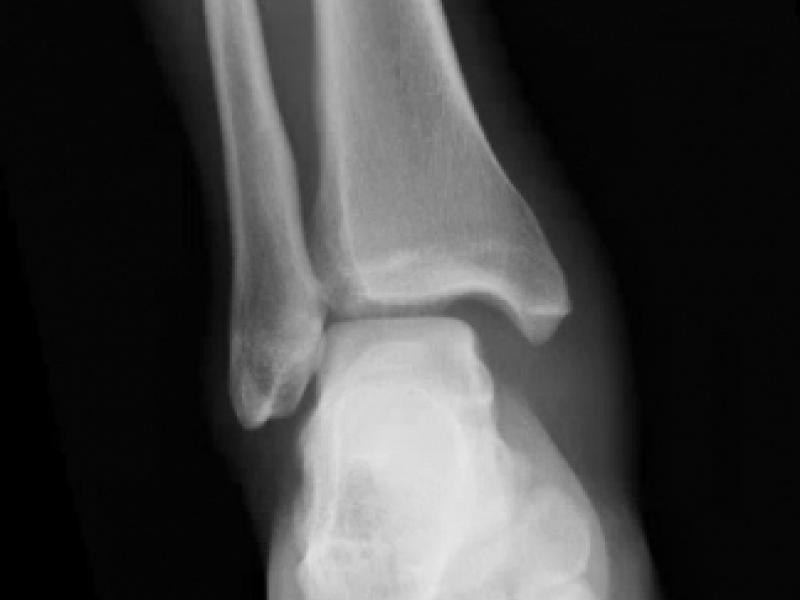

What's the diagnosis?  By Dr. Michael Tom

A 24 yo male presents with ankle pain after attempting a